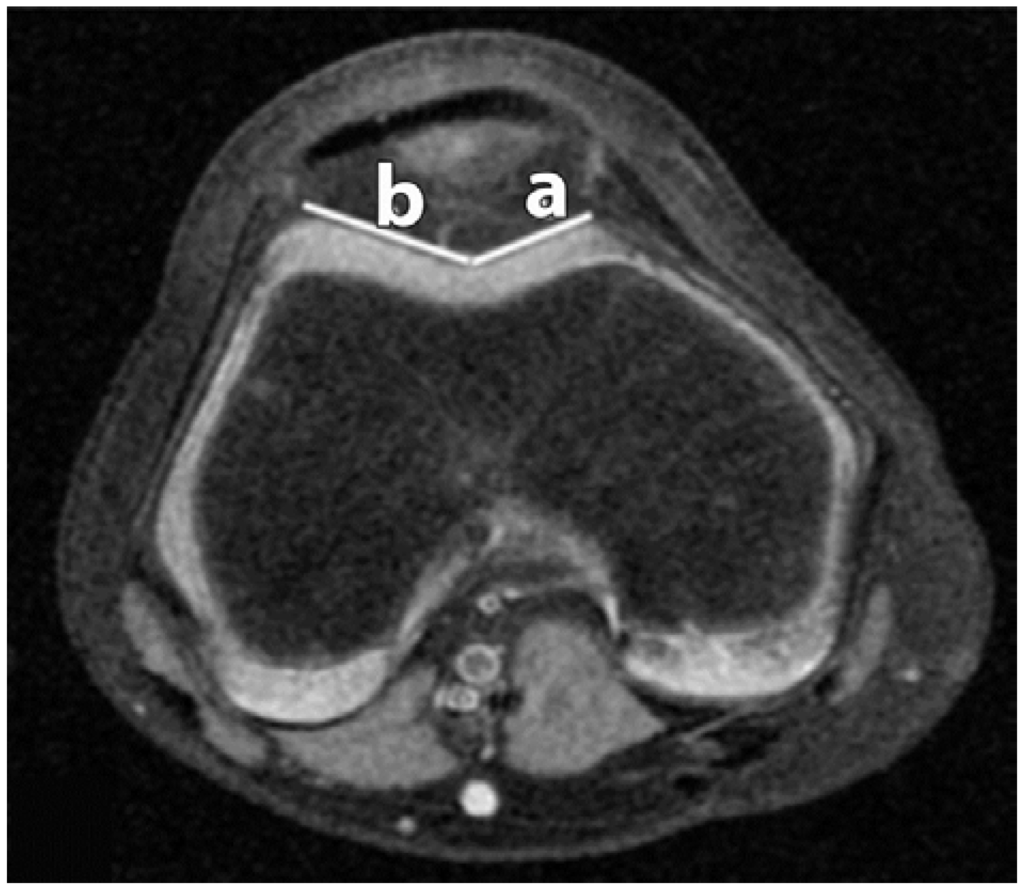

Figure 2.

Trochlear Facet Asymmetry (TFA). The distances of the lateral facet (b); and medial facet (a) are recorded.